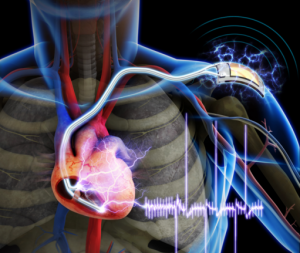

kalp pili Etiketli Yazılar